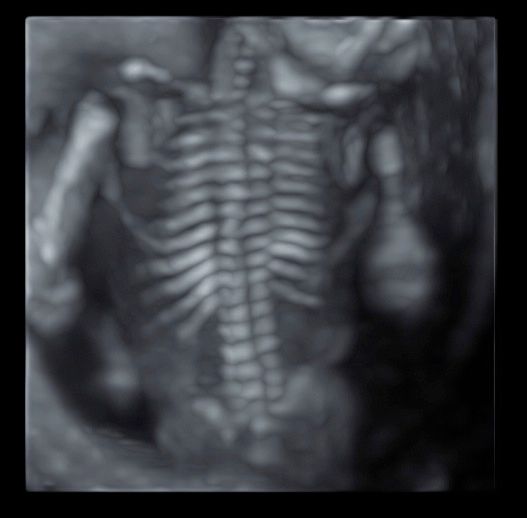

Foto e video

• Ecocardiografia fetale

• Ecografia morfologica